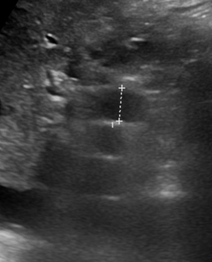

Abdominal CT scan. Hemorrhagic rupture of a simple hepatic cyst without active hemorrhage. The presence of free intraperitoneal fluid is noted (Courtesy Dr. V. Penopoulos)